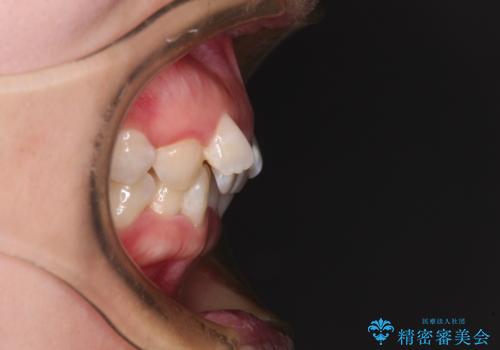

- 上下前歯のデコボコを気にして来院された患者様です。

口元の突出感はあまりなかったものの、デコボコを非抜歯で改善すると出っ歯になる可能性があるため、上下左右の第一小臼歯4本を抜歯し、ワイヤー装置にて矯正治療を行うこととしました。